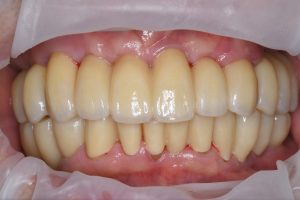

昨年フルマウスの方の定期検診

ネジの緩みもなく、値も良い

よく磨けている💪長持ちさせましょう!